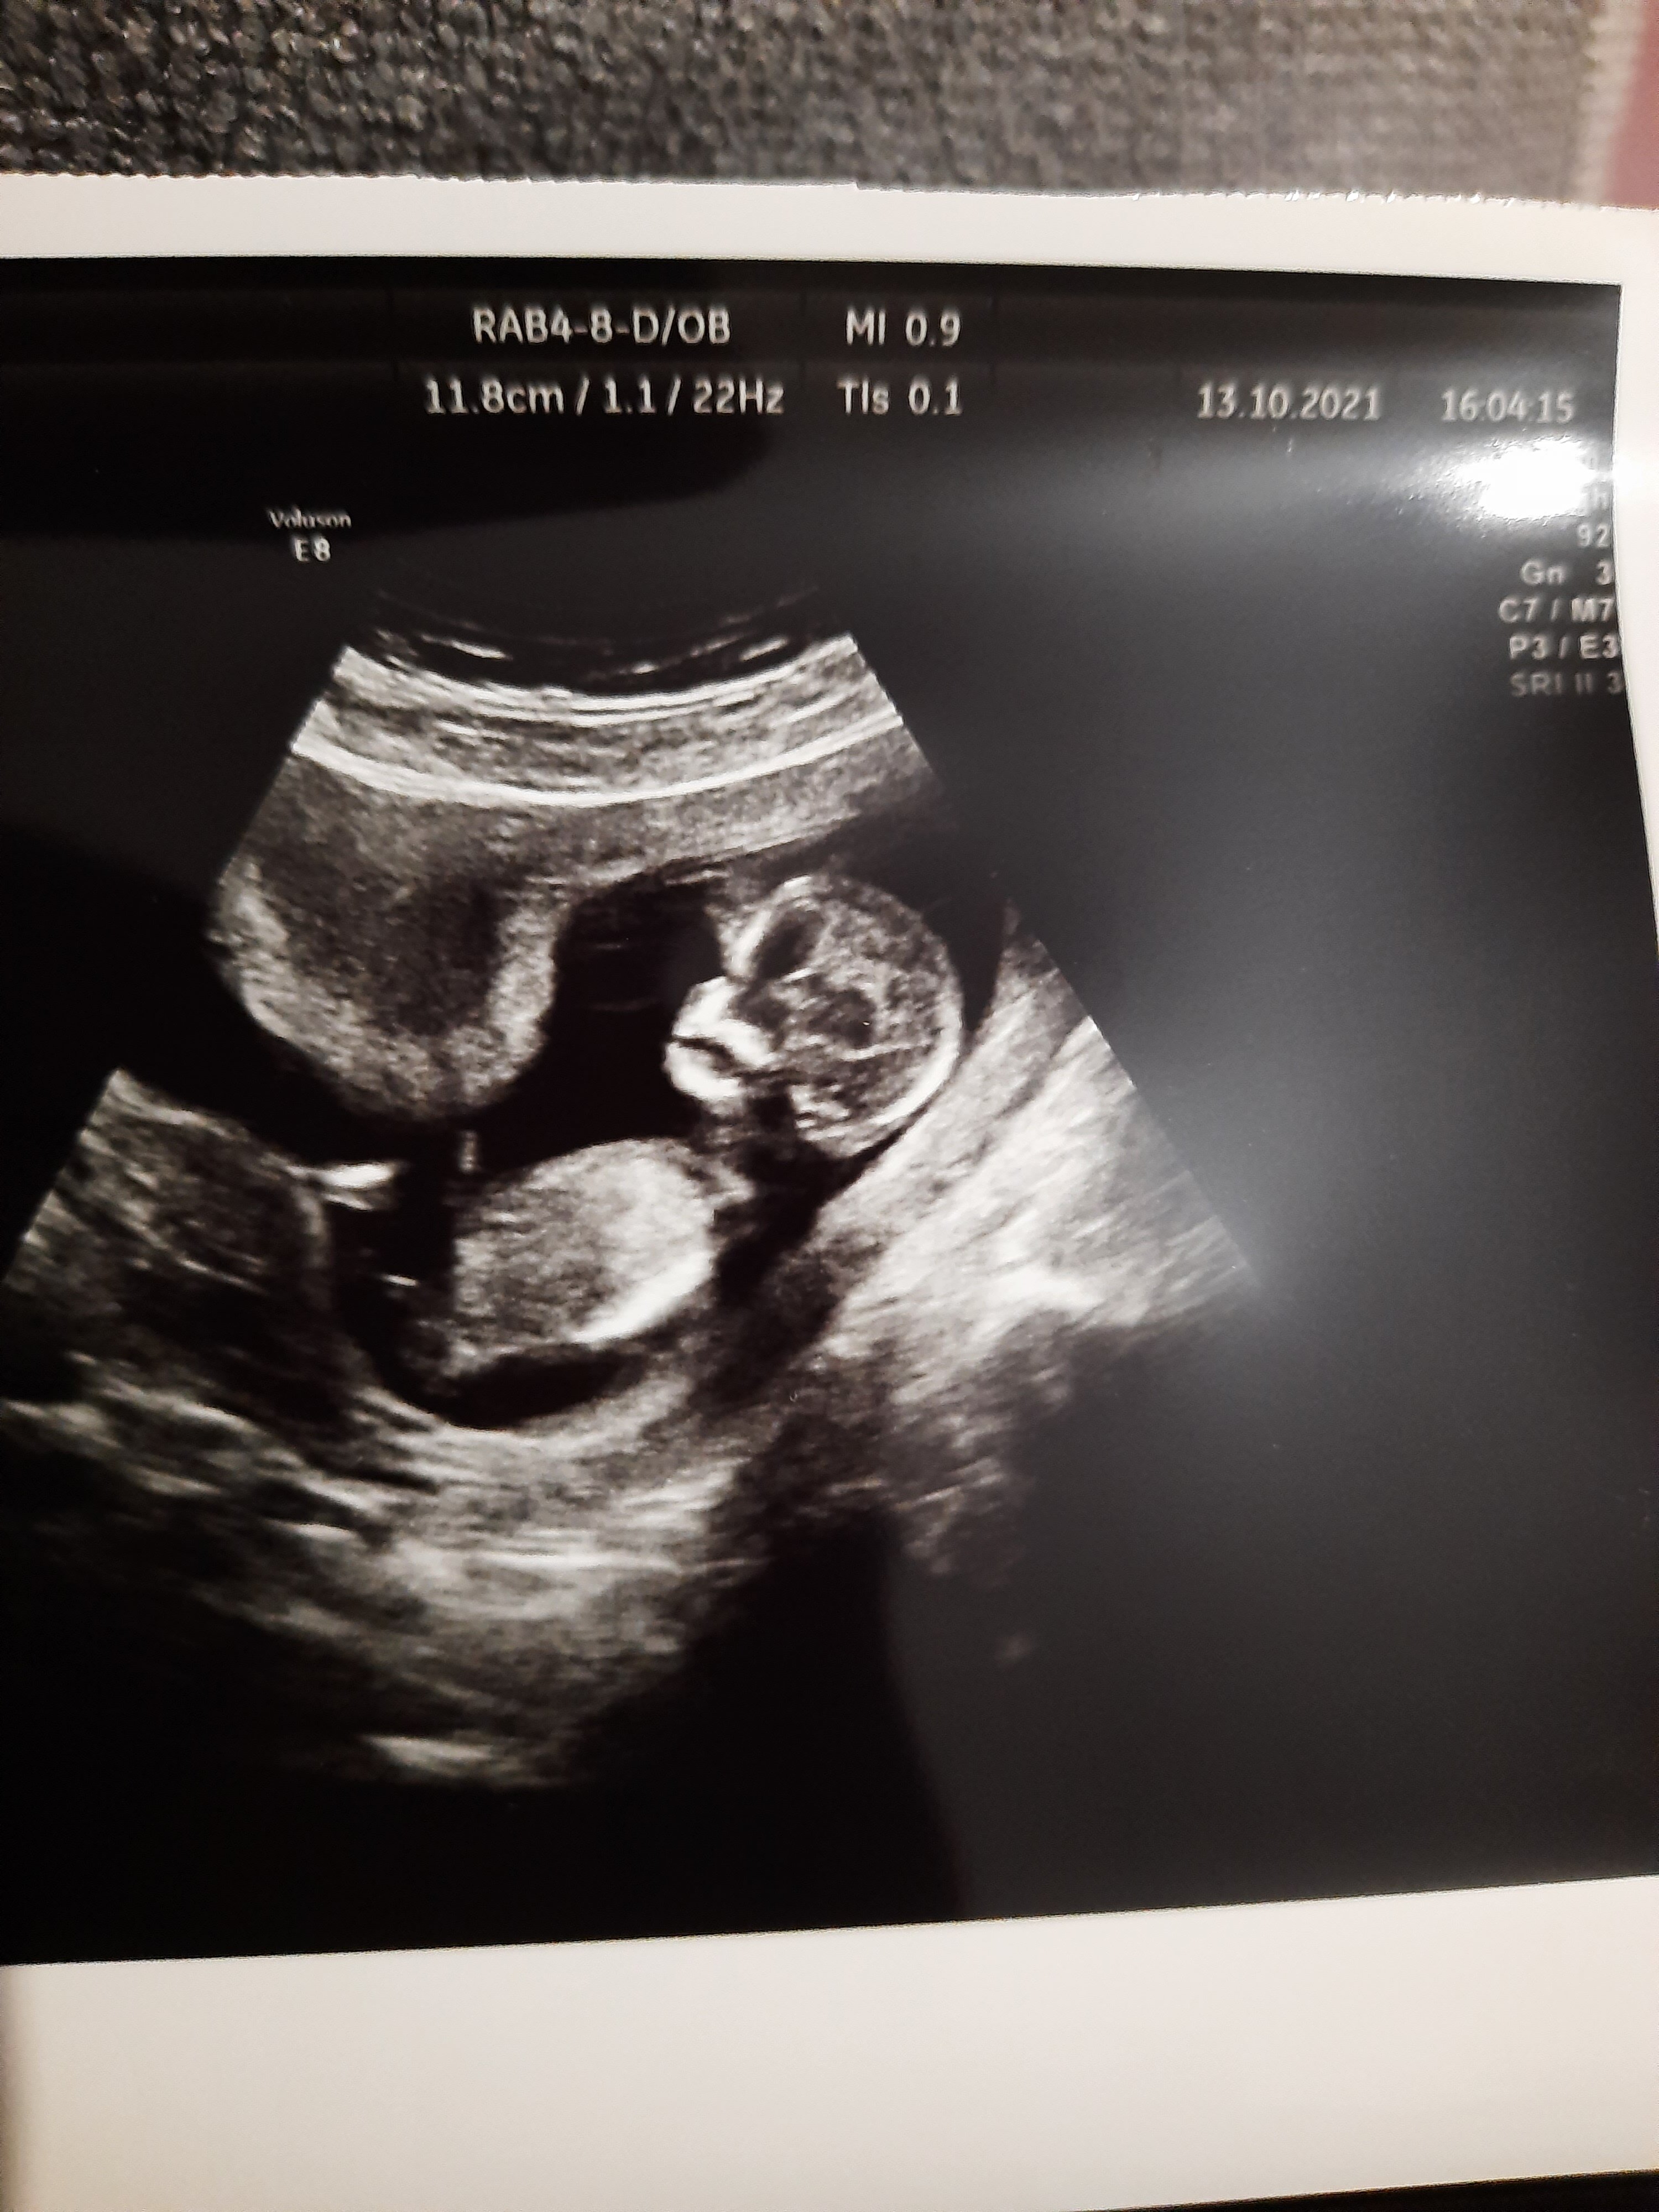

Nic się nie przejmuj taki wynik wychodzi większości i dzieciaki wszystkie zdrowe. Czytałam.nawet dziś na innym forum właśnie najwięcej pow. 100 mamy przerażone, nastraszone i zdrowe po tych oczywiście płatnych badaniachJa pier… dostałam wiadomość od lekarza w sprawie wyników Pappy… Zobacz załącznik 1326436

Ja pier… dostałam wiadomość od lekarza w sprawie wyników Pappy… Zobacz załącznik 1326436